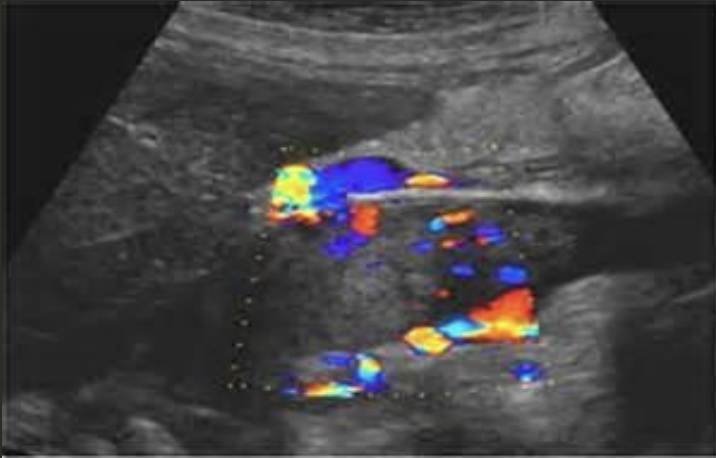

Pseudoaneurysm → rupture from intima layer contained in deeper layers of artery wall

2D US presentation: heterogenous, pulsating central structure with internal swirling of brighter echogenicity

color doppler: “yin-yang” sign, “to and fro” PW waveform

DDX: hematoma (hypoechoic intraluminal echoes, but not color flow or neck connecting), true aneurysm (wide rather than narrow neck continuous w/ artery, chronic rather than acute)